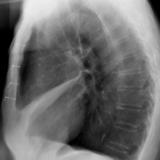

Case 1 Lateral

Date: 02/28/2004

Views: 3190